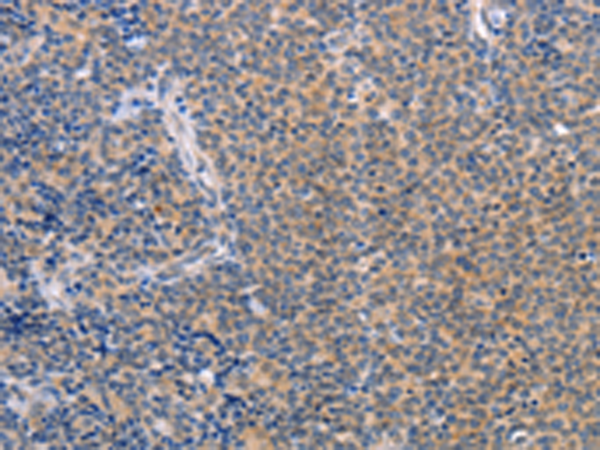

分类: 科研抗体货号: P11628别名: LEC; LMC; NCC4; CKb12; HCC-4; LCC-1; Mtn-1; NCC-4; SCYL4; ILINCK; SCYA16应用: WB,IHC反应种属: Human

分类: 科研抗体货号: P11640别名: T10应用: WB,IHC反应种属: Human

分类: 科研抗体货号: P11626别名: KRS1; MST2/KRS2; MST1; YSK3; TIIAC应用: WB,IHC反应种属: Human, Mouse

分类: 科研抗体货号: P11638别名: CD327; CD33L; OBBP1; CD33L1; CD33L2; CDW327应用: WB,IHC反应种属: Human

分类: 科研抗体货号: P11636别名: LY94; CD335; NKP46; NK-p46应用: WB,IHC反应种属: Human, Mouse

分类: 科研抗体货号: P11664别名: CIB; CIBP; KIP1; PRKDCIP; SIP2-28应用: IHC反应种属: Human, Mouse, Rat

分类: 科研抗体货号: P11634别名: CD30; Ki-1; D1S166E应用: IHC反应种属: Human